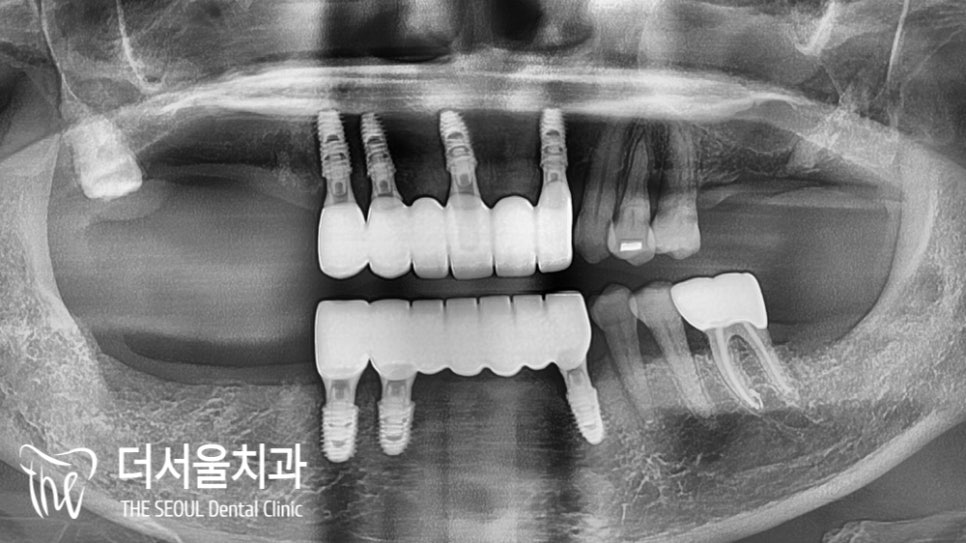

수정구치과 에서는 컴퓨터 분석을 통해

식립 될 위치를 결정한 다음,

본격적인 수술 단계로 들어갔습니다.

조직과 주변 치아들, 치조골을 분석한 뒤

픽스쳐가 심어질 위치를 결정했는데요.

이후 순차적인 식립을 도와드렸습니다.

몇 달이 지나고, 최종 보철을 올릴 날이 되었는데요.

박 원장이 강조했던 그 포인트 그대로

잘 재현된 것을 확인할 수 있었습니다.

형태 및 색조, 크기는 물론이며

교합까지 알맞게 잘 맞고 있는 모습이네요.

절단 기능을 하는데도 문제가 없을 정도로

자연치와 같이 만들어졌는데요.